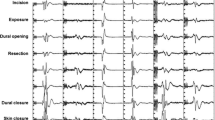

All neurophysiological recordings were performed using a Medtronic NIM Eclipse Neurological Workstation (Medtronic, Minneapolis, MN). Data collection and interpretation was performed by trained intraoperative neurophysiologists employed by Tel Aviv Medical Center. Multiple ION techniques were utilized, and a general outline is described in Table 1.

Direct cortical motor evoked potentials (dcMEP): following the phase reversal technique, the silastic-embedded subdural strip was maintained over the primary motor cortex, for intermittent stimulation (0.2 Hz) and MEP recording from the identical muscles as cortical MEP described above. Stimulation was carried out using two neighboring contacts immediately anterior to the location of the phase reversal waveform, as described above. Stimulation intensities were restricted to a maximum of 25 mA, and cathodal return was placed at the Fz scalp position using a subdermal needle electrode. Baseline dcMEPs were established prior to any surgical manipulation and were compared with all subsequent recordings to identify potential deterioration.

ION methodologies were applied during surgery in a tailored approach relative to the surgical stages. A general outline is described in Table 1.

tcMEP and dcMEP techniques were utilized in 26 and 37 cases, respectively. Both tcMEP and dcMEP were utilized in 16 cases.

Immediate postoperative neurological data was fully available for 18/26 and 26/37 patients with tcMEP and dcMEP data, respectively. Two patients with SMA syndrome were excluded from the analysis. We found a significant negative correlation between intraoperative dcMEP stability and clinical motor decline (p < 0.001). The sensitivity, specificity, and positive and negative predictive values of significant dcMEP attenuation for new postoperative deficit were 100%, 78%, 60%, and 100%, respectively (Table 3).

Similar to dcMEP stability, tcMEP stability also correlated with motor decline (p = 0.005). The sensitivity, specificity, positive predictive value, and negative predictive value were 66%, 100%, 100%, and 86%, respectively (Table 4).